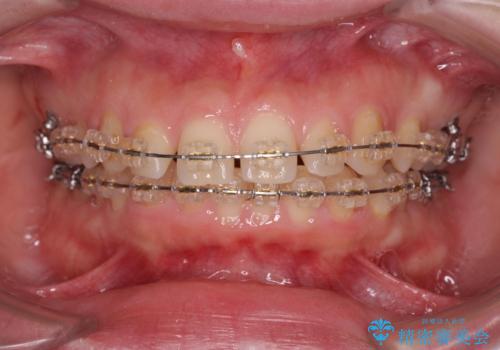

- 矯正装置

- ワイヤー矯正

ワイヤーを用いたマルチブラケット矯正を行うことで深い噛み合わせを改善し、前歯の隙間もなくし審美的な歯列へと治療をおこなっていきます。